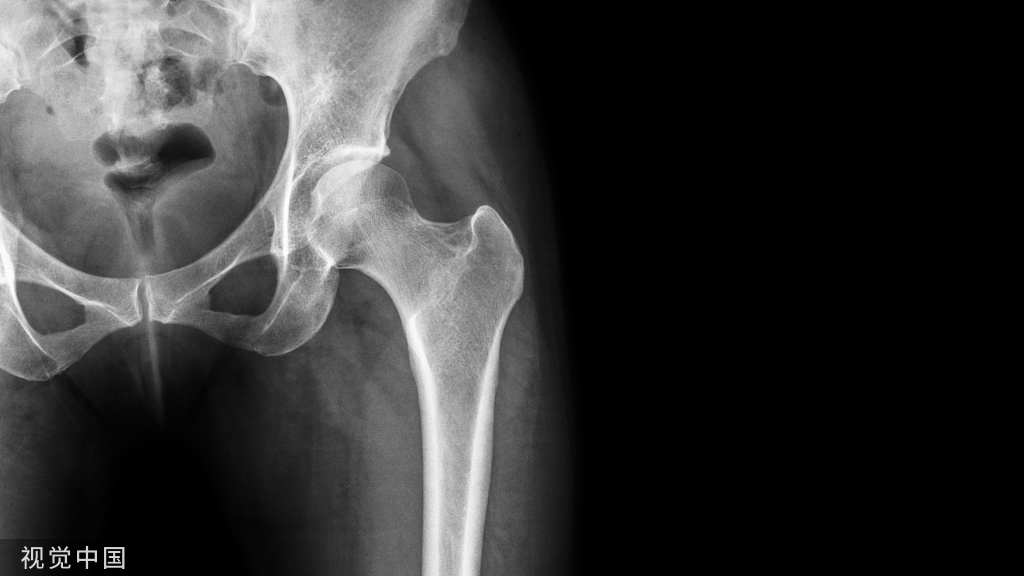

股骨颈骨折是临床较常见的骨折,发病率约占髋部骨折的50%,最常见于骨质疏松老年患者,多由跌倒等低能量损伤引起,年轻人股骨颈骨折发生率较低,多由车祸、高处坠落等高能量损伤引起。目前股骨颈骨折的治疗方案多种多样,然而在临床诊治中还存在诸多问题。随着人口老龄化进程的加快,股骨颈骨折发生也迅速增多。